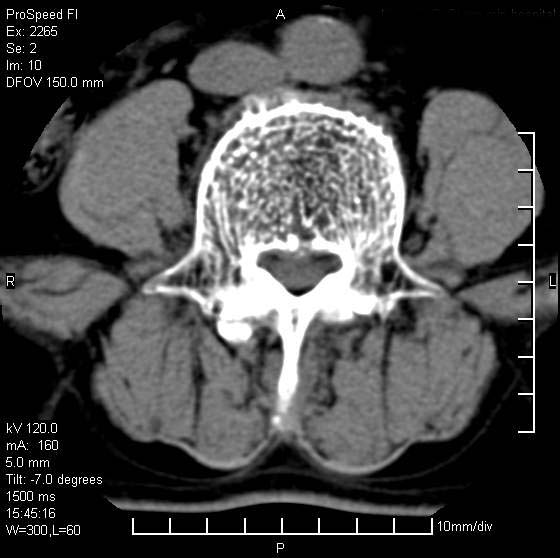

以下是引用qiushi在2007-8-22 17:26:00的发言:[br]没骨窗![br] 1、 l5~s1间盘膨出伴轻度突出(中央型)、变性。[br] 2、l4~5间盘膨出伴突出(右侧远外侧型)。[br] 3、l3~4间盘膨出。[br] 4、腰椎退行性变。[br]

以下是引用随缘的人在2007-8-22 20:56:00的发言:[br]腰椎退行性变:1。l4/5,l5/s1膨出[br] 2。l5/s1间盘退行性变 [br] 3。腰椎骨质增生

以下是引用liaizhi在2007-8-22 22:13:00的发言:[br]1,l4-5锥间盘膨出,2,l5-s1椎间盘膨出并退变(椎间盘呈真空征);3,血管瘤(椎体骨小梁稀疏粗大)?